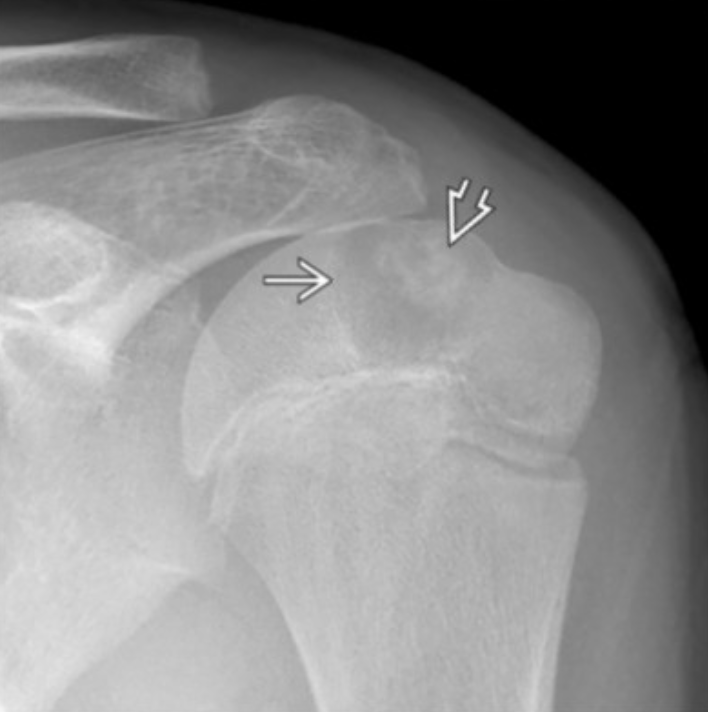

Ewing Sarcoma

• Permeative lesion with onion skin periostitis - bone may look essentially normal!!!!

• Diaphysis & flat bones (scapula)

• Large soft tissue component